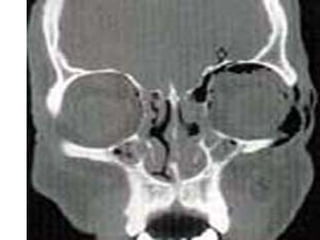

Radiographic Evaluation

• CT scan of the orbits

• Plain films not useful due to a high rate of

false negatives and non-diagnostic studies